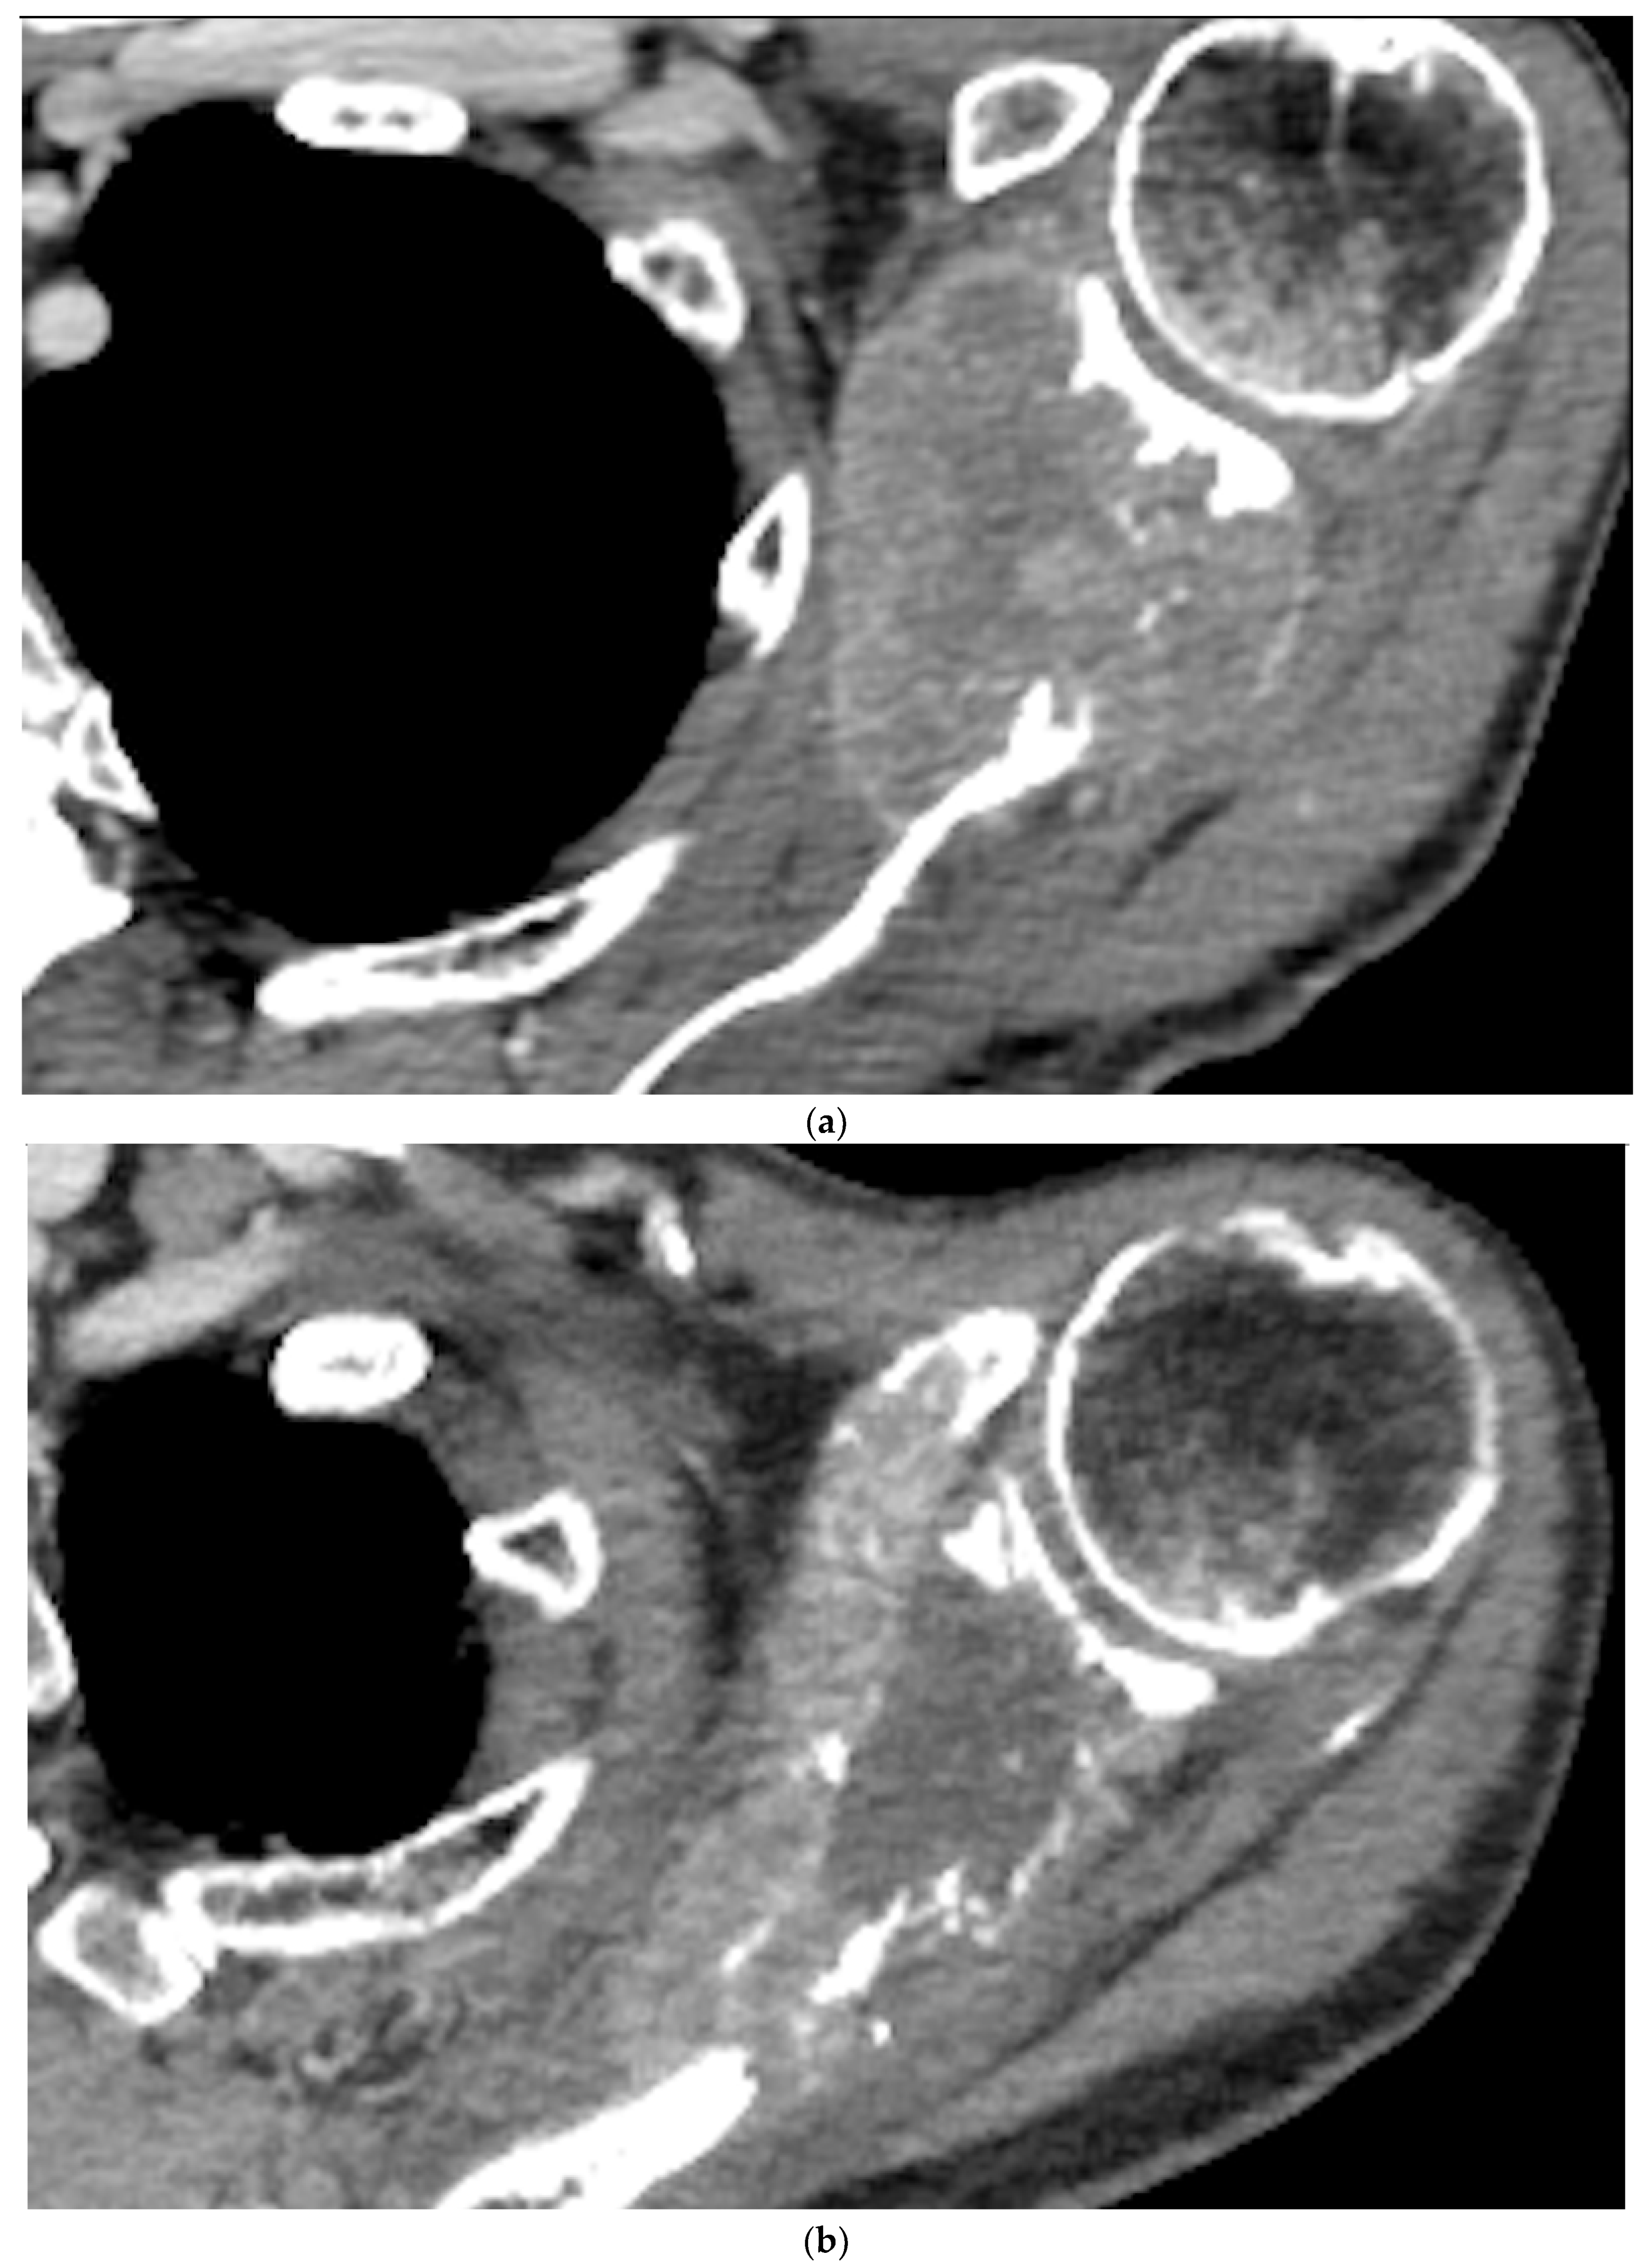

Metastatic tumor size was reduced from a mean of 192.2 cm3 (range 38.7 to 480.1 cm3) pre-embolization to a mean of 177.3 cm3 (range 37.2 to 455.5 cm3) at the 12-month follow-up (p<0.05) (Figure 3). None of the patients experienced embolization-related complications.

Figure 3. a) Pre-embolization CT showing a metastatic lesion from renal cancer in the body of the scapula and b) 12-month post-embolization CT showing increased ossification of the lytic lesion of the scapula, with significant reduction of extraskeletal pathologic tissue. c) and d) illustration of the evolution of a metastatic lesion of the scapula before and after arterial embolization.